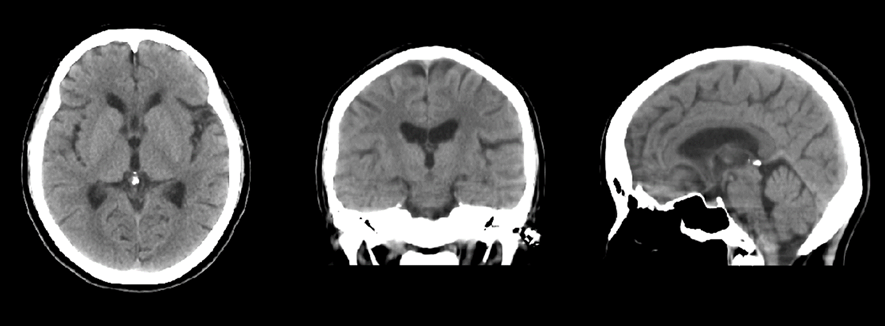

従来のチルトコンベンショナルスキャンによる頭部検査では、脳底部、特に脳幹、小脳付近の画質はあまり良いとは言えませんでした。それがRevolution ACTでは、1.25mmスライスでのヘリカルスキャンができるので、薄いスライスでの収集による効果でアーチファクトが軽減され、また連続したデータであることからMPR(サジタル面、コロナル面)での画質が格段に向上しました。その結果、小脳、脳幹部の診断への信頼度が上がり、また、海馬領もコロナル面での観察が容易にでき、臨床有用性を高めています。

cv_uchida_04_big.png